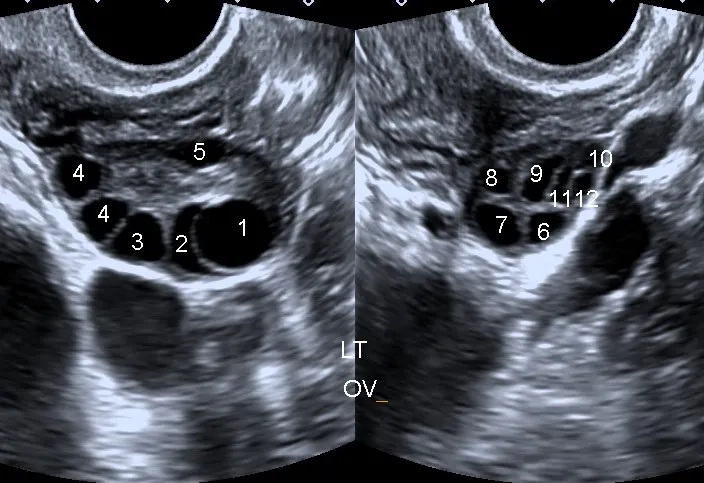

Image illustrating the hormonal effects of Polycystic Ovary Syndrome